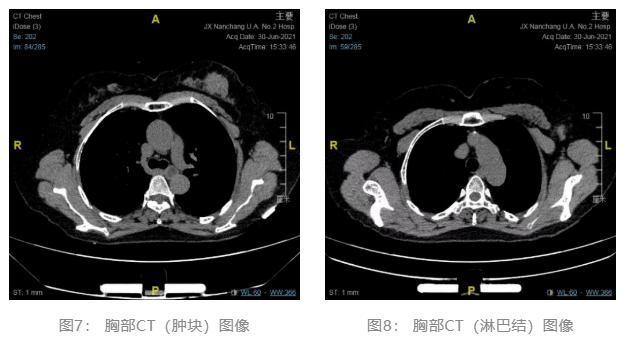

2021.06.30 胸部CT平扫:1.左乳占位伴左侧腋窝区肿大淋巴结 2.双肺未见明显异常(图7、8)